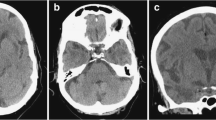

Prenatal and neonatal intracerebral hemorrhage (ICH) and encephaloclastic porencephaly are frequently associated with mutations in both COL4A1 and COL4A2 [18, 20,21,22]. Their most common cause is a germinal matrix hemorrhage leading to deep venous infarction involving the basal ganglia and frontal lobe, tissue necrosis, and porencephalic cavitation (Fig. 1). Prenatal ICH size correlates clinically with motor outcomes [22]. Extensive bilateral porencephaly also resembles hydranencephaly.

A 3-year-old, male patient with COL4A1-related disorder. a Axial non-contrast computed tomography demonstrated calcification along the bilateral occipital horns of the lateral ventricles (arrows) and asymmetrical ventricular enlargement. b-e Axial T2-weighted imaging and coronal FLAIR imaging revealed porencephaly in the bilateral frontal lobes, asymmetrical ventricular enlargement, hyperintensities in the bilateral basal ganglia, thalami, deep white matter, and cerebellar dysplasia. Note also the implanted intraocular lens for cataracts (arrows). f Axial T2*-weighted imaging demonstrated multiple microbleeds in the splenium of the corpus callosum and subcortical and deep white matter

Other types of brain lesion related to prenatal hemorrhage have been reported in mutations in children, such as abnormal basal ganglia, dysplastic brain stem, cerebellar hemorrhage, cerebellar hypoplasia/atrophy, brain calcification, ventricular asymmetry, mild ventriculomegaly, and hydrocephalus (Figs. 1, 2) [18, 26, 27] while Dandy-Walker malformation may occur prenatally [28].